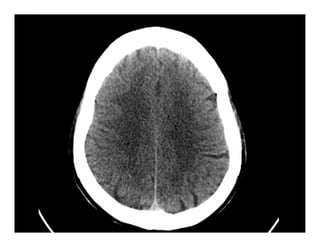

GIẢI PHẪU HÌNH ẢNH

SỌ NÃO

Giải phẫu hình ảnh sọ não

(1): Bao trong

(2): Đầu nhân đuôi

(3): Nhân bèo

(4): Đồi thị

(5): Não thất III

(6): Sừng trán não

thất bên

Giải phẫu

2

3

4

5

6

1

Tổn thương